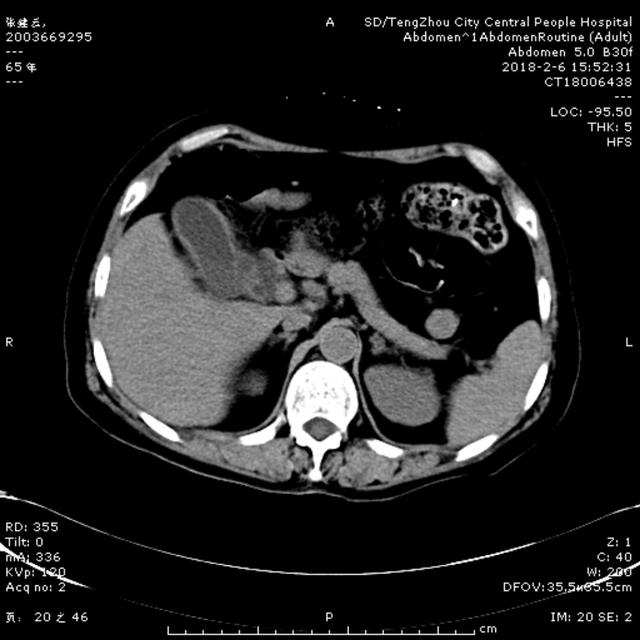

2月6日15:00,一65歲女性患者,因腹痛5天,伴寒戰,發熱,惡心,嘔吐,在當地診所治療,效果差,以“腹痛待查”收住消化內二科。入院查體:體溫37.1℃ 血壓140/90mmHg,急性病容,鞏膜輕度黃染,心肺未及異常,腹部平坦,右上腹壓痛伴反跳痛,肝區叩擊痛陽性,雙下肢無水腫。入院后給予抗炎、補液處理。急查肝功示谷丙轉氨酶561U/L, 谷草轉氨酶798U/L, 總膽紅素64.9umol/L ,直接膽紅素58.9umol/L,血常規示白細胞5.44X10^9/L, 中性粒細胞4.69X10^9/L,凝血常規示正常,行腹部CT可見膽囊壁增厚,膽總管擴張,考慮膽系感染、 膽總管結石可能性大。